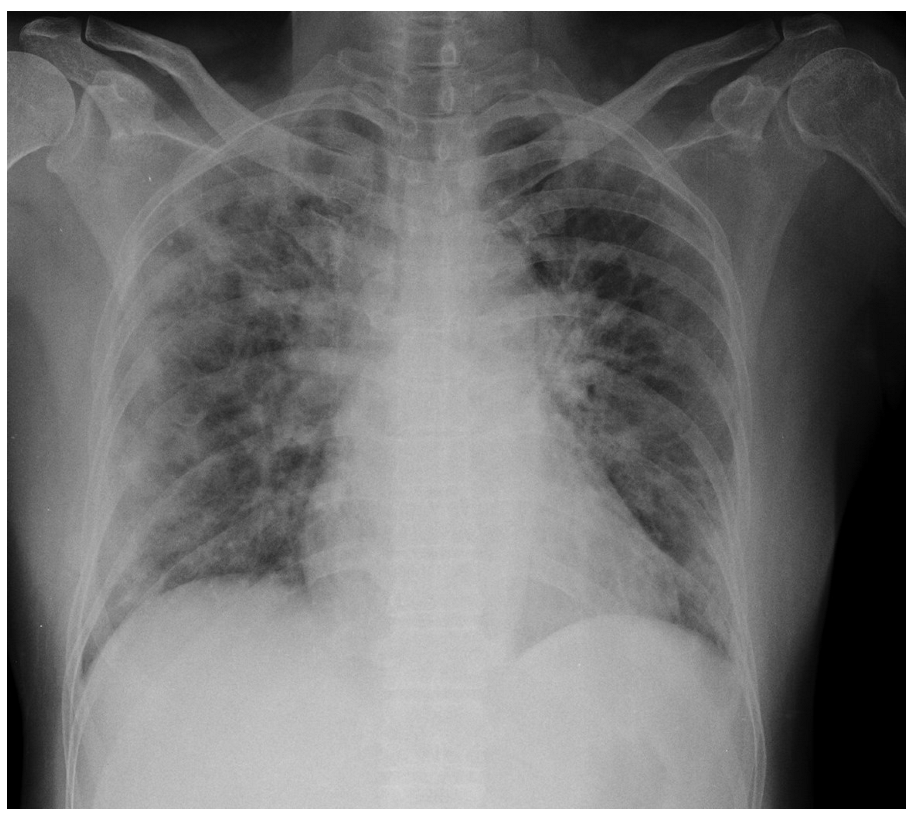

For a more intuitive understanding, we visualize a sample of each category in Figure 9, Figure 10 and Figure 11.

Figure 11. Normal sample: X-ray Image dataset.

Applsci 13 00454 g011